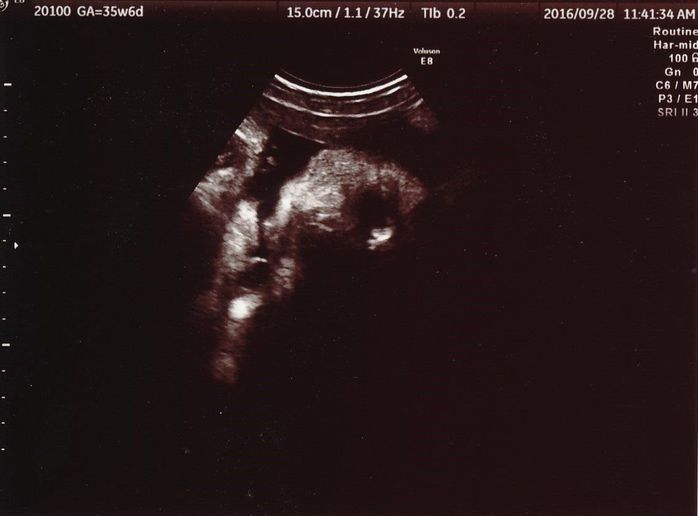

妊娠35週目のエコー写真

残念ながらこのときも、赤ちゃんは顔をよく見せてはくれませんでした。中央に顔、右目が黒く鼻が白く写っています。頭が右で顎が左です。顔の左上に右手、左手を口の近くに持ってきているので、また指しゃぶりをしていたのでしょう。